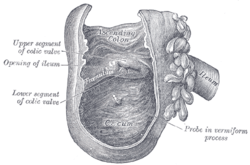

The last part of the small intestine is the ileum. This also contains villi and vitamin B12; bile acids and any residue nutrients are absorbed here. When the chyme is exhausted of its nutrients the remaining waste material changes into the semi-solids called feces, which pass to the large intestine, where bacteria in the gut flora further break down residual proteins and starches.[30]

Cecum

The cecum is a pouch marking the division between the small intestine and the large intestine.[31] The cecum receives chyme from the last part of the small intestine, the ileum, and connects to the ascending colon of the large intestine. At this junction there is a sphincter or valve, the ileocecal valve which slows the passage of chyme from the ileum, allowing further digestion. It is also the site of the appendix attachment.